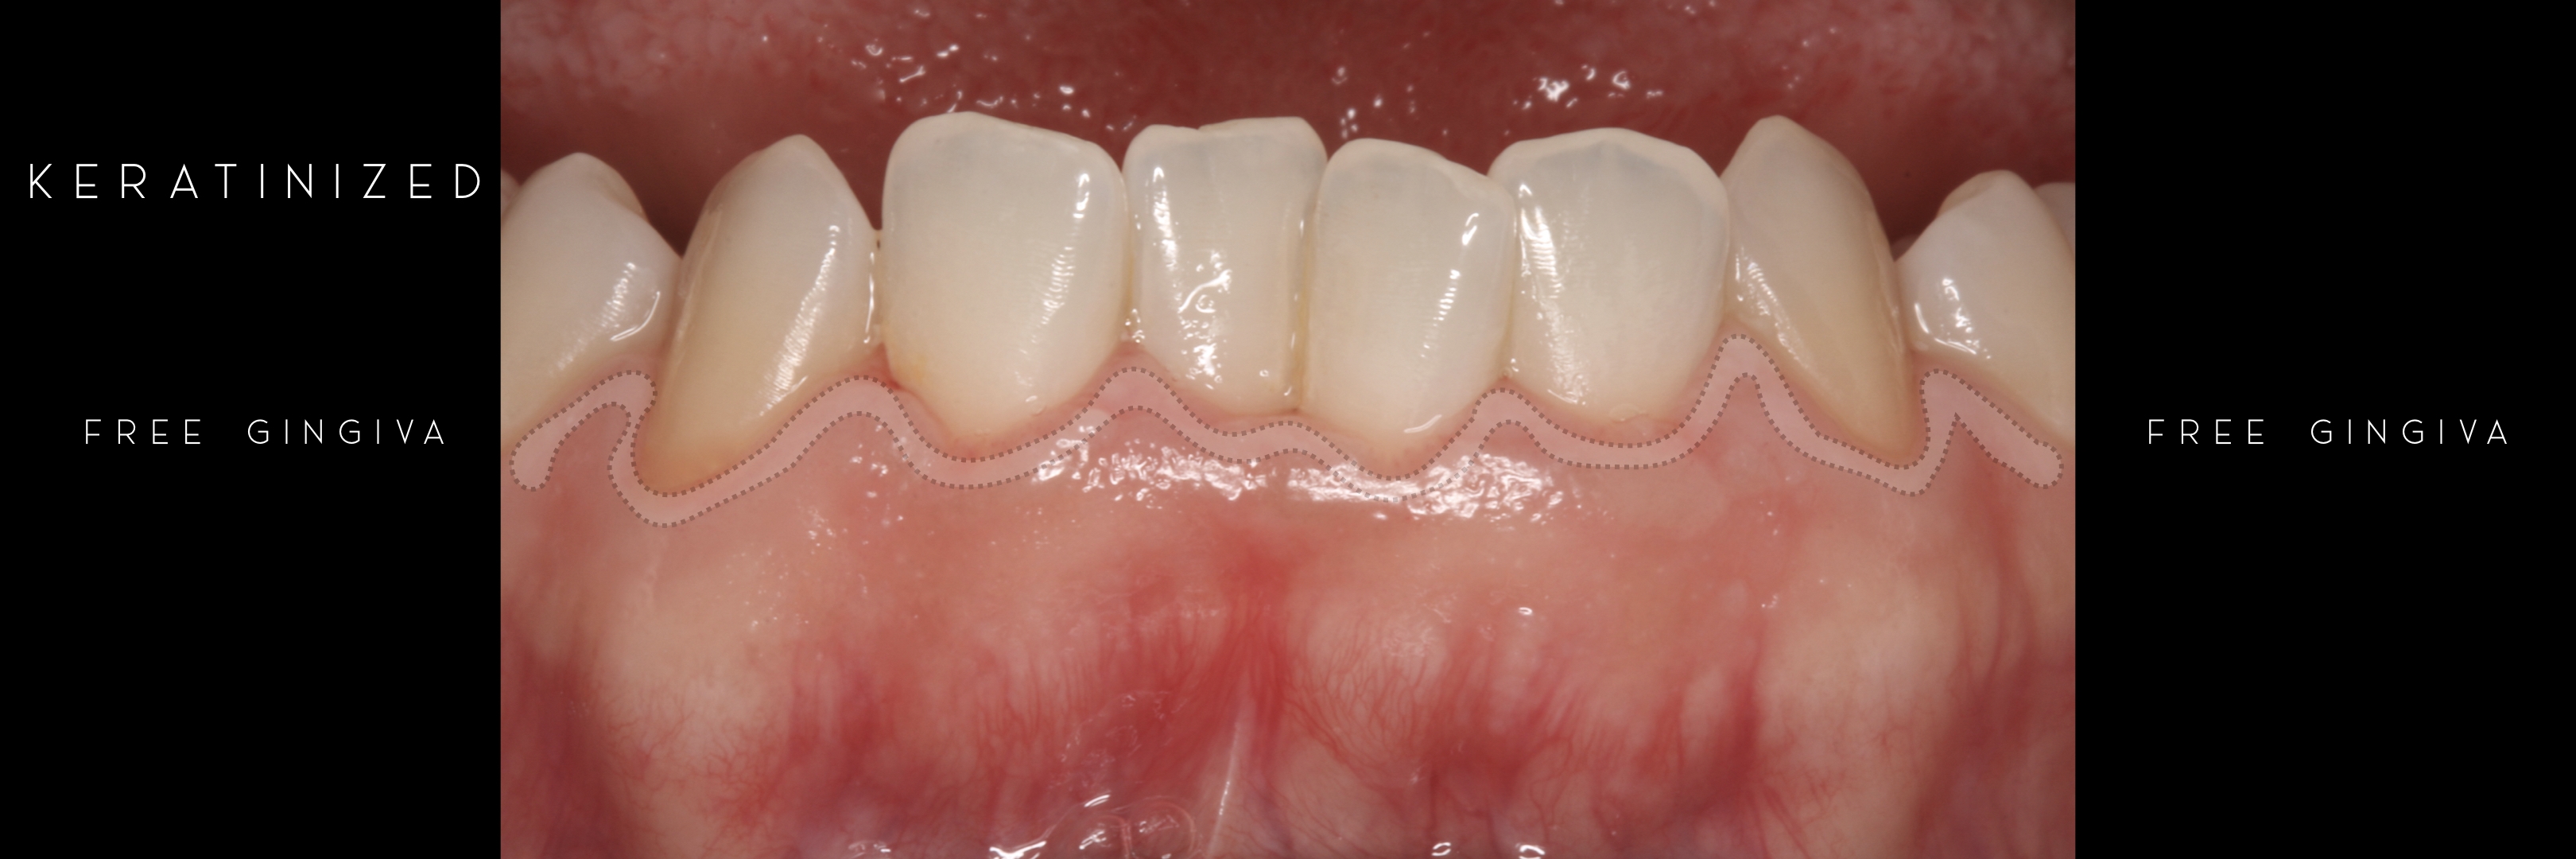

KERATINIZED gingiva includes

the free gingiva

(marginal gingiva & papillae)

and the attached gingiva extending from the gingival mar­gin to the mucogingival junction.

However free marginal gingiva is different in characteristics on its outer and inner surfaces: outer surface is keratinized;

inner surface is

non-keratinized, constituting part of the gingival sulcus.